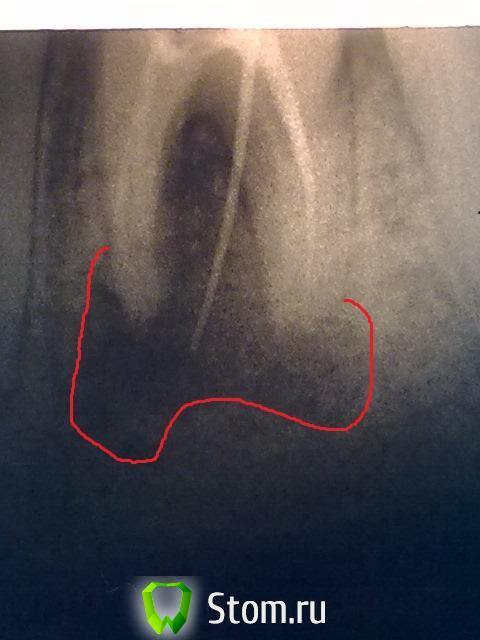

Рустам Опубликовано 7 февраля, 2012 Поделиться Опубликовано 7 февраля, 2012 Обратилась пациентка 27-ми лет с жалобами на наличие свищевого хода(периодически происходит отток экссудата) в области 4.6. Объективно 4.6 ранее лечен по осложненному кариесу, пломба на оклюзионной и медиальной поверхностях неудовлетворительного качества. Перкуссия слабо болезненная. Подвижность 1-ой степени. Пальпация переходной складки в проекции верхушек корней 4.6 слабо болезненная. Открытый свищевой ход по центру коронки зуба ниже края десны на 3 мм. Сделана диагностическая рентгенограмма с введенным в свищевой ход гуттаперчевым штифтом. Имеются проблемы как в области верхушек корней так и в области бифуркации. Пациентка в ближайшее время планирует беременность, обратилась с целью плановой санации. Есть ли смысл пытаться спасать такой зуб? Качественное эндо сделать могу. Отсутствующих зубов в полости рта нет. Или лучше не рисковать, удалить и после родов имплантант?P.S. Снимок не лучшего качества, на телефон и ассистент только учиться. Ссылка на комментарий

Рустам Опубликовано 14 августа, 2013 Автор Поделиться Опубликовано 14 августа, 2013 (изменено) Пришла пациентка на прием, прошло 1,5 года после того как мы пролечили ей проблемный 4.6. Лечение 4.6 было закончено 17.02.2012 г., на устья жидкотекучий, пломба "Харизма", объяснил что при положительной рентгенологической картине в динамике, будем протезировать вкв + м/к, после родов. Девушка родила мальчика, сейчас кормит грудью 2,5 мес..Можно ли сейчас приступать к протезированию? Как считаете?http://img-fotki.yandex.ru/get/9153/22303897.13/0_a23fc_4cbe6812_XL.jpghttp://fotki.yandex.ru/users/rrustam2004/view/664572/смущает небольшое разрежение в области фуркации, и кажется несостоятельность пломбы медиально, хотя во рту все бледно розовое и при зондировании все ок.Перфораций в области фуркации не было.http://img-fotki.yandex.ru/get/9489/22303897.13/0_a23fd_8ce72d3d_XL.jpghttp://fotki.yandex.ru/users/rrustam2004/view/664573/ Изменено 14 августа, 2013 пользователем Рустам 1 Ссылка на комментарий